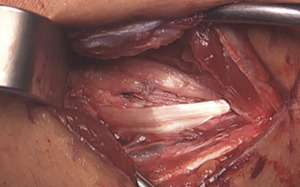

The posterior raphe of the flexor mass is split longitudinally along the length of the skin incision. The split utilizes the interval between the flexor digitorum superficialis (FDS) and flexor carpi ulnaris (FCU). During exposure, care is taken to preserve the anterior fascial layer of the FCU to protect both the muscle and the ulnar nerve.

After exposing the anterior bundle of the medial UCL, the ulnar nerve is internally decompressed by incising the overlying fascia of the FCU along its course down to the concavity of the proximal ulna.

Beginning distally at the sublime tubercle, the ligament is split longitudinally proximally to the ligament footprint origin at the base of the medial epicondyle. The ligament is explored for any acute injury pattern. Additional suturing may be employed for distinct proximal and distal tears.